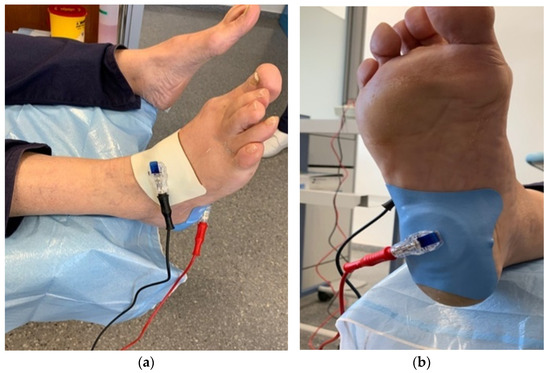

Alternative treatment for plantar fasciitis cheap